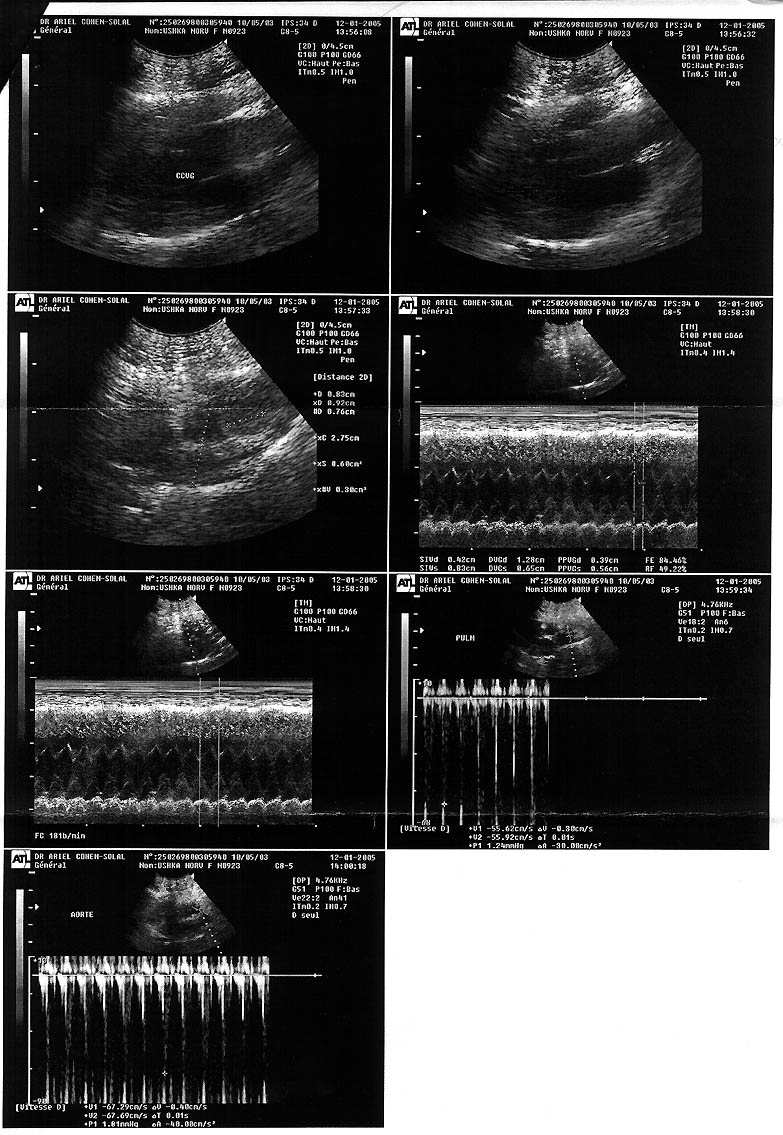

Marie-Pierre François | 10/05/2003 | first premier |

light septal defect (acquired origin) légère anomalie septale (origine acquise) |

normal | 1.5 years / ans |